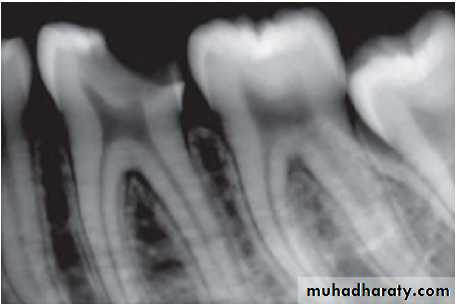

• Radiographic changes show:

– Chronic apical periodontitis in longstanding cases.

– In young patients, low grade longstanding irritation stimulates periapical bone deposition, i.e. condensing osteitis. Radiograph shows areas of dense bone around apices of involved teeth.